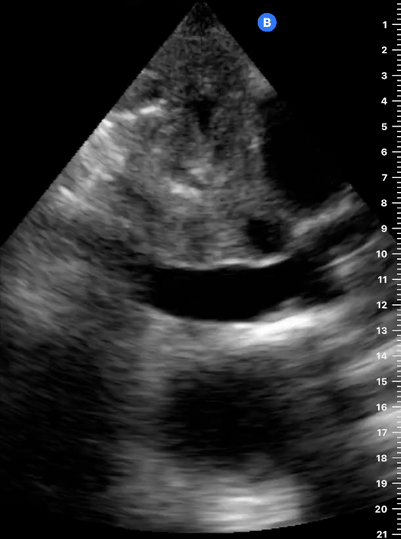

THE VIEWS

The A4C view provides an accurate chamber size comparison. However, achieving a proper A4C view (avoiding foreshortening or ballooning, and visualising the four chambers with a vertically oriented interventricular septum) can be a challenging exercise of image acquisition. Additionally, the PSAX view at the level of the papillary muscles shows both LV and RV side by side and is useful to assess function and size. When RV pressure is high, the septum will be pushed and flattened towards the LV, resulting in the characteristic “D-shaped” LV or “D sign”.